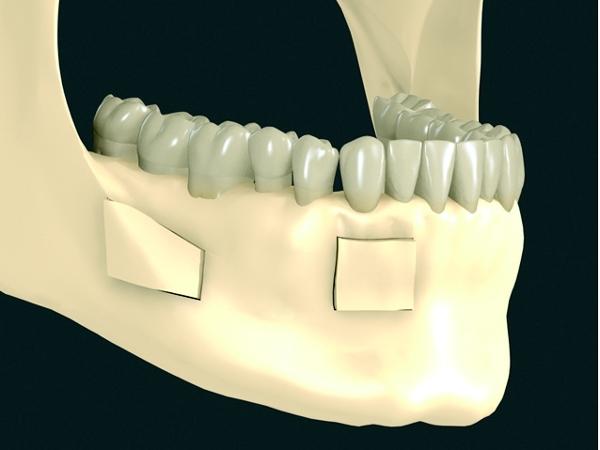

Sterowana regeneracja kości. Poszerzenie wyrostka zębodołowego żuchwy.